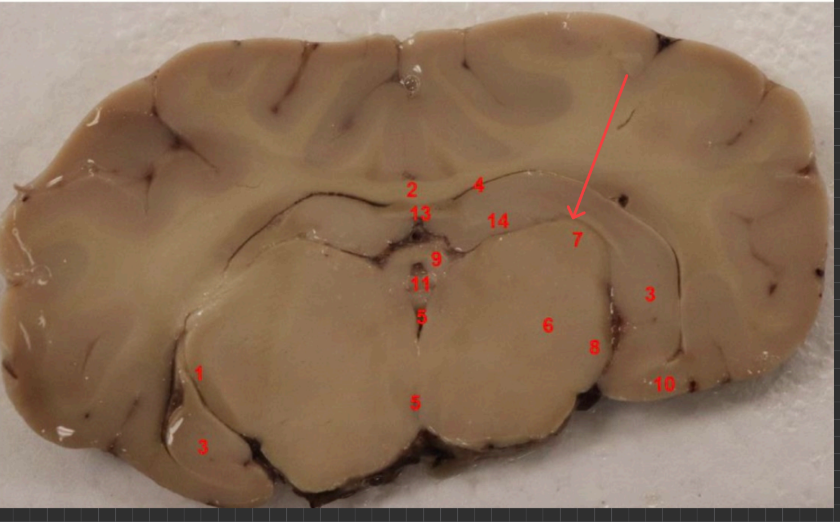

thalamus

what is this

posterior commissure

splenium of corpus callosum

superior colliculs

cerebral aqueduct

periaqueductal gray

superior colliculus

red nucleus

what is this, function

ventral tegmental area , brain's reward system, motivation, and emotion regulation

substaina nigra, regulates voluntary movement, motor planning, reward-seeking, and addiction

cerebral punducle

what is this, function?

dorsal raphe nucleus , serotonin, (mood, sleep, emotion)

what is this , function

locus coerules , regulating arousal, wakefulness, attention, and stress responses

dorsal raphe nucleus

superior cerebellar punudcle, inferior cerebellar punducle

what is this , function?

Reticular formation arousal, consuoiunsess, sleepwake ( keeps u awake!!!)